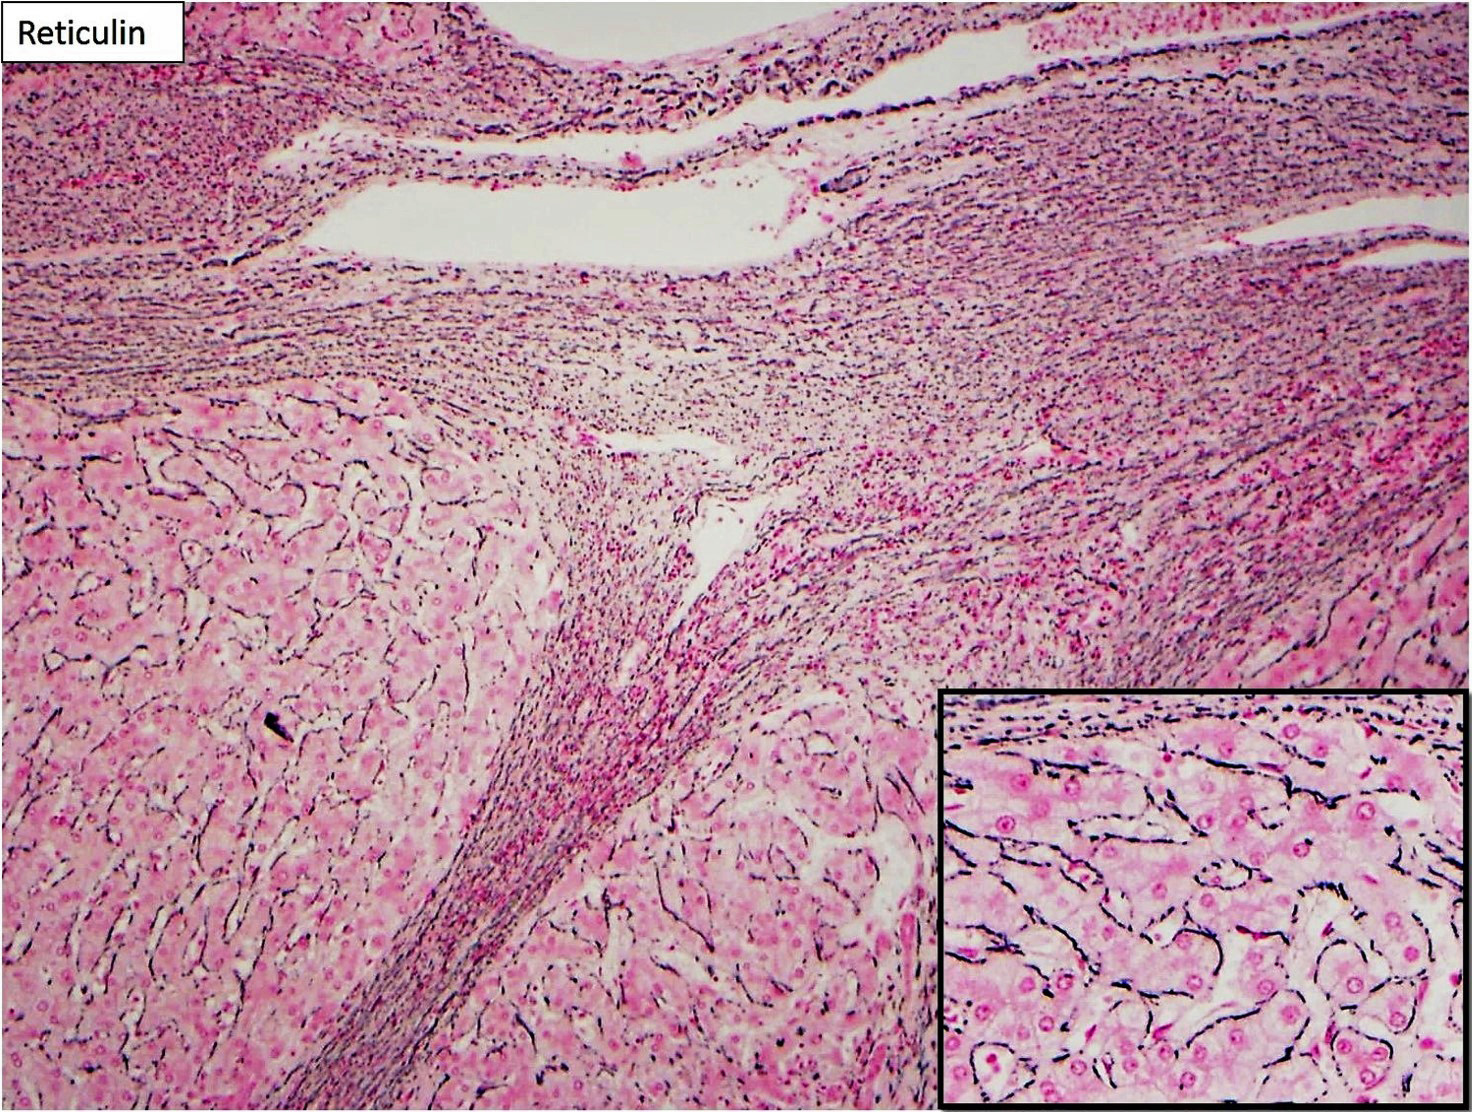

Focal nodular hyperplasia (FNH) is reactive lesion that is composed of hepatocytes and bands of fibrosis that occur due to vascular shunting in noncirrhotic liver. Usually FNH is a single lesion that most often seen in young and middle-aged women. Macroscopically, it is well-demarcated tan sub capsular mass with central stellate scar. Histologically, on low magnifications, it resembles cirrhosis with nodularity and band of fibrosis. The hepatocytes lack cytologic atypia. Multifocal areas of bile ductular proliferation (metaplasia) often seen at the interface of the hepatic parenchyma and the fibrous bands. Abnormal thick walled arteries are present in the center of the fibrous bands. Glutamine synthetase immunohistochemical stain shows an irregular blotchy/patchy pattern “maplikepattern”. While it has diffuse staining pattern in both hepatic adenomas (Beta catenin mutated) and HCC. The lesional cell show shows low proliferation index by Ki 67 immunohistochemical stain (<1%). Glypican-3 immunostain is negative. Reticulin special stain demonstrates normal reticulin pattern. It was hypothesized that FNH might be a precursor to FLC. However, there has been no proof until now to support this idea. The FNH that surrounds a small subset of FLC considers as a reaction to the tumor itself and not a precursor. [6]

Hepatic adenomas (except the androgen related subtype) and FNH do not have cytologic atypia or mitosis. They both usually occur in young middle-aged women. While FNH do not has malignant potential, 10% of the hepatic adenoma reported to in the literature have underwent malignant transformation. Inflammatory/ telangiectatic adenoma might be somehow a challenge to differentiate from FNH (especially on biopsy). The bile ductular proliferation in the inflammatory/telangiectatic hepatic adenoma is typically patchy and located in faux portal tracts and not fibrous bands. They typically have dilated (telangiectatic) and congested sinusoids, with large aberrant arteries in the parenchyma. They might have inflammation (but not seen in all cases). This type of adenoma is positive for serum amyloid A (which is negative in the normal liver). Some cases might also be Beta Catenin nuclear positivity; which then will be called Inflammatory/telangiectatic hepatic adenoma with Beta catenin activation. Glutamine synthetase is negative in the inflammatory/telangiectatic type, while it shows map like pattern in FNH. It could be positive in Beta catenin mutated type.